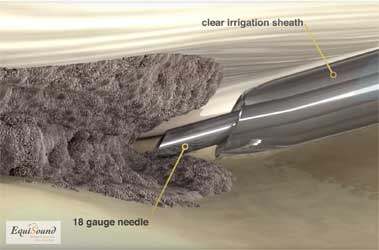

Tenex is een behandelingstechniek die 5j geleden ontwikkeld werd in USA om chronische peesaandoeningen te behandelen bij mensen (chronische achillespezen, hielspoor, patellapeesdegeneratie etc). De techniek maakt gebruik van ultrason geluid (zoals bij het verwijderen van tandsteen) om beschadigd weefsel af te breken en zo het genezingsproces te stimuleren en een nieuwe herstelkans te geven. De geluidsfrequentie is specifiek gekozen om enkel harde weefsels (fibrose en mineralisaties) af te breken en geen schade aan te brengen aan gezond peesweefsel. De ultrason behandeling wordt toegediend door middel van een holle naald in een holle buis (zie foto 9a). Uit de holle naald komt tijdens de behandeling een influx van NaCl dewelke tegelijk geaspireerd wordt door de holle buis (foto 9b en 9c). Het water zorgt in eerste instantie voor de afvoer van gedebrideerd weefsel, maar tegelijk ook voor afkoeling van de naald dewelke erg opwarmt door het ultrason proces.

Doordat de naald echogeleid ingebracht wordt via steekincisies in de huid, is deze behandeling minimaal-invasief. Zo recupereert de patiënt sneller en is er weinig wondzorg nodig. Ook zorgt dit voor een exacte plaatsing van de naald in het degeneratieve gebied van de pathologische structuur.